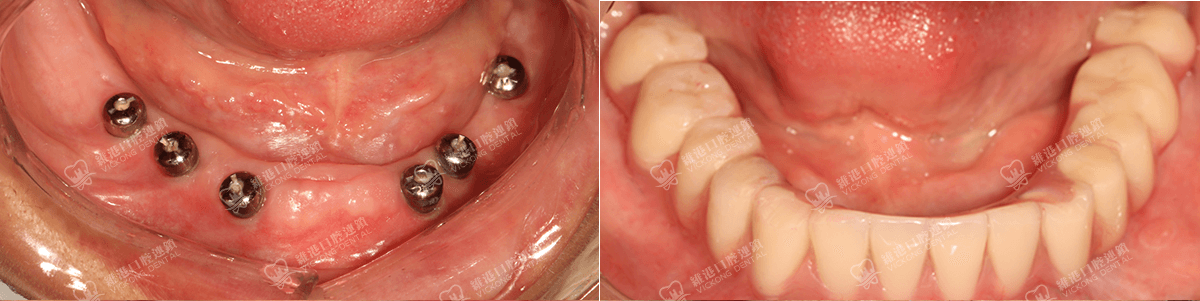

奧齒泰授權“CA親水”種植中心

美國HIOSSEN授權種植中心

種植數字化修復指定合作單位

諾貝爾全球質保機構

諾貝爾全球植牙中心

瑞典諾貝爾種植系統授權機構

瑞士ITI種植系統技術合作單位